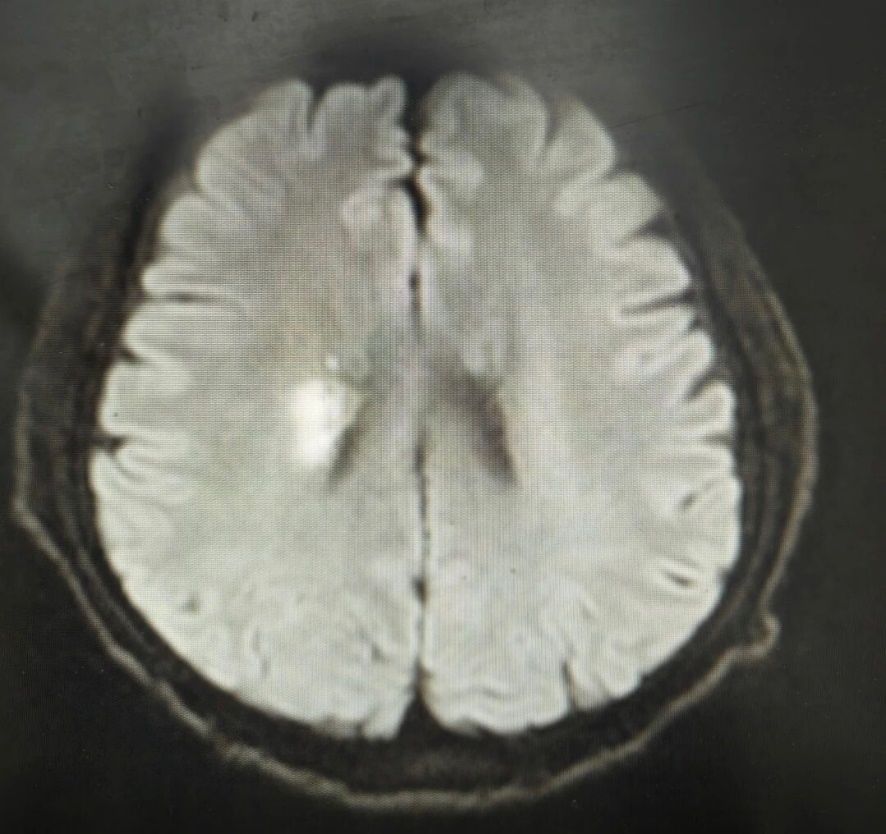

急诊医生结合其病史及症状,高度怀疑再次突发脑梗死,护士随即协助完善头颅CT等溶栓前检查,急诊科同步联系神经内科医生会诊、开辟急诊绿色通道。

确诊急性脑梗死后,医生第一时间耐心告知家属诊疗方案:“目前患者确诊急性脑梗死,我们已联系会诊、开辟绿色通道,转运中会全程监护,请放心”,同时俯身叮嘱李先生:“我们送您去进一步治疗,好好配合,路上不舒服就拉我们一下”。